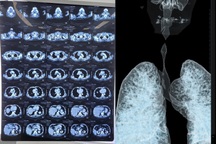

Chia sẻ với Dân trí, bác sĩ Nguyễn Thắng Nhật Tuệ, Trưởng khoa Cấp cứu, người bệnh có tiền sử bệnh gout và rối loạn mỡ máu. Anh được đưa vào viện trong tình trạng hôn mê sâu, ngưng tim, ngưng thở, tím tái, đồng tử giãn 4-5 mm, không phản xạ ánh sáng.

Dù các bác sĩ đã nỗ lực hồi sức tim phổi hơn một giờ bằng ép tim ngoài lồng ngực, đặt nội khí quản, bóp bóng, sốc điện và dùng thuốc, người bệnh vẫn không xuất hiện tín hiệu sự sống.